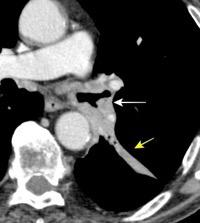

30 años

Borramiento de la banda PARA-aórtica por AdenoCa. de LII, no visible en 2005

Colapso de LII. TC: secreciones bronquiales.

Endoscopia tapón mucopurulento extraído

Borramiento parcial por Ca. epidermoide.